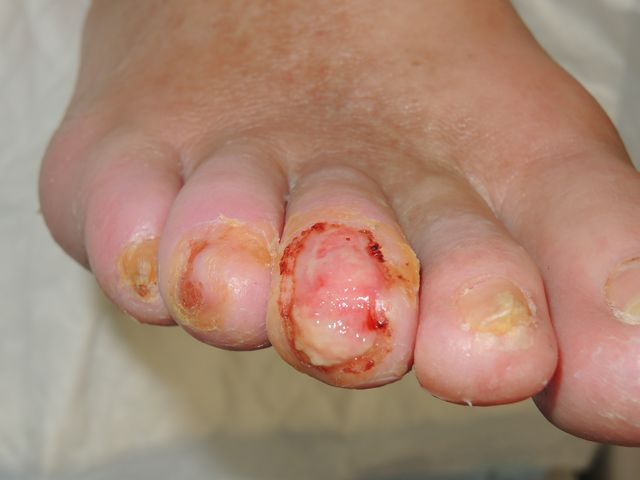

Ulceraciones en pie diabético.